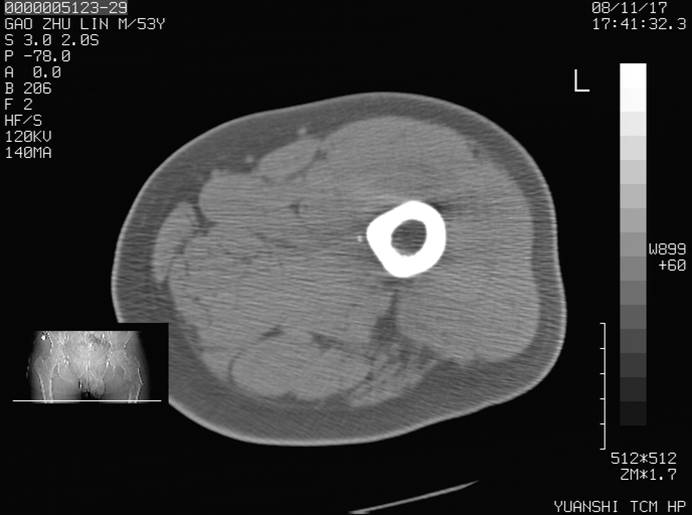

标题: CT16696:M53Y,左股骨上段骨折。 [打印本页]

标题: CT16696:M53Y,左股骨上段骨折。

左股骨上段外伤1个小时,左股骨上段疼痛。村医以腰椎间盘病变给以按摩及理疗数天。

图像不太清楚,左股骨上段外伤性骨折?病理性骨折?

左股骨上段粉碎性骨折

左股骨上段粉碎性骨折;建议上传骨窗看看是不是病理性的啊!

左股骨上段粉碎性骨折,不排除病理性骨折可能。

考虑骨肉瘤伴病理骨折

考虑:骨肉瘤伴病理骨折.

病理性骨折,考虑转移所致.

左股骨上段粉碎性骨折,不排除病理性骨折可能